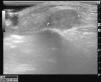

Pruebas complementariasLas radiografías de cara, órbita, hendidura esfenoidal y cráneo fueron normales. La ecografía de partes blandas mostraba una tumoración redondeada y sólida con algún vaso de pequeño calibre en el tejido celular subcutáneo (fig. 2).